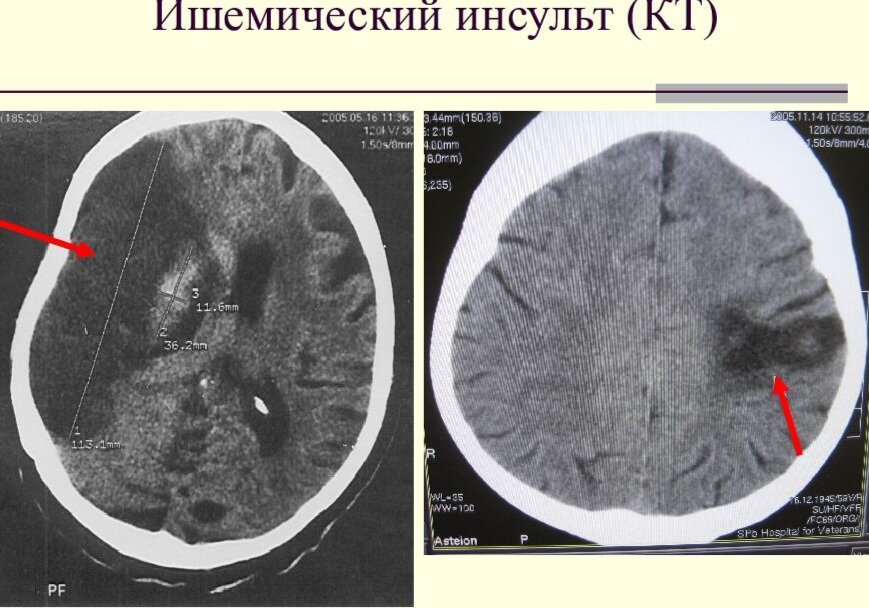

Современные технологии компьютерной томографии: Новое средство борьбы с инсультом головного мозга

2. Уникальность и преимущества КТ в диагностике: важность своевременного обнаружения инсульта, так как чем раньше начнется лечение, тем меньше возможны его последствия. КТ позволяет выявлять даже небольшие сосудистые нарушения и определять вид инсульта.

3. Возможности КТ в оценке степени повреждения головного мозга и планировании лечения: различные методы и техники КТ позволяют анализировать области поражения и определять, насколько серьезным является инсульт, что помогает врачам создать индивидуальный план реабилитации для каждого пациента.